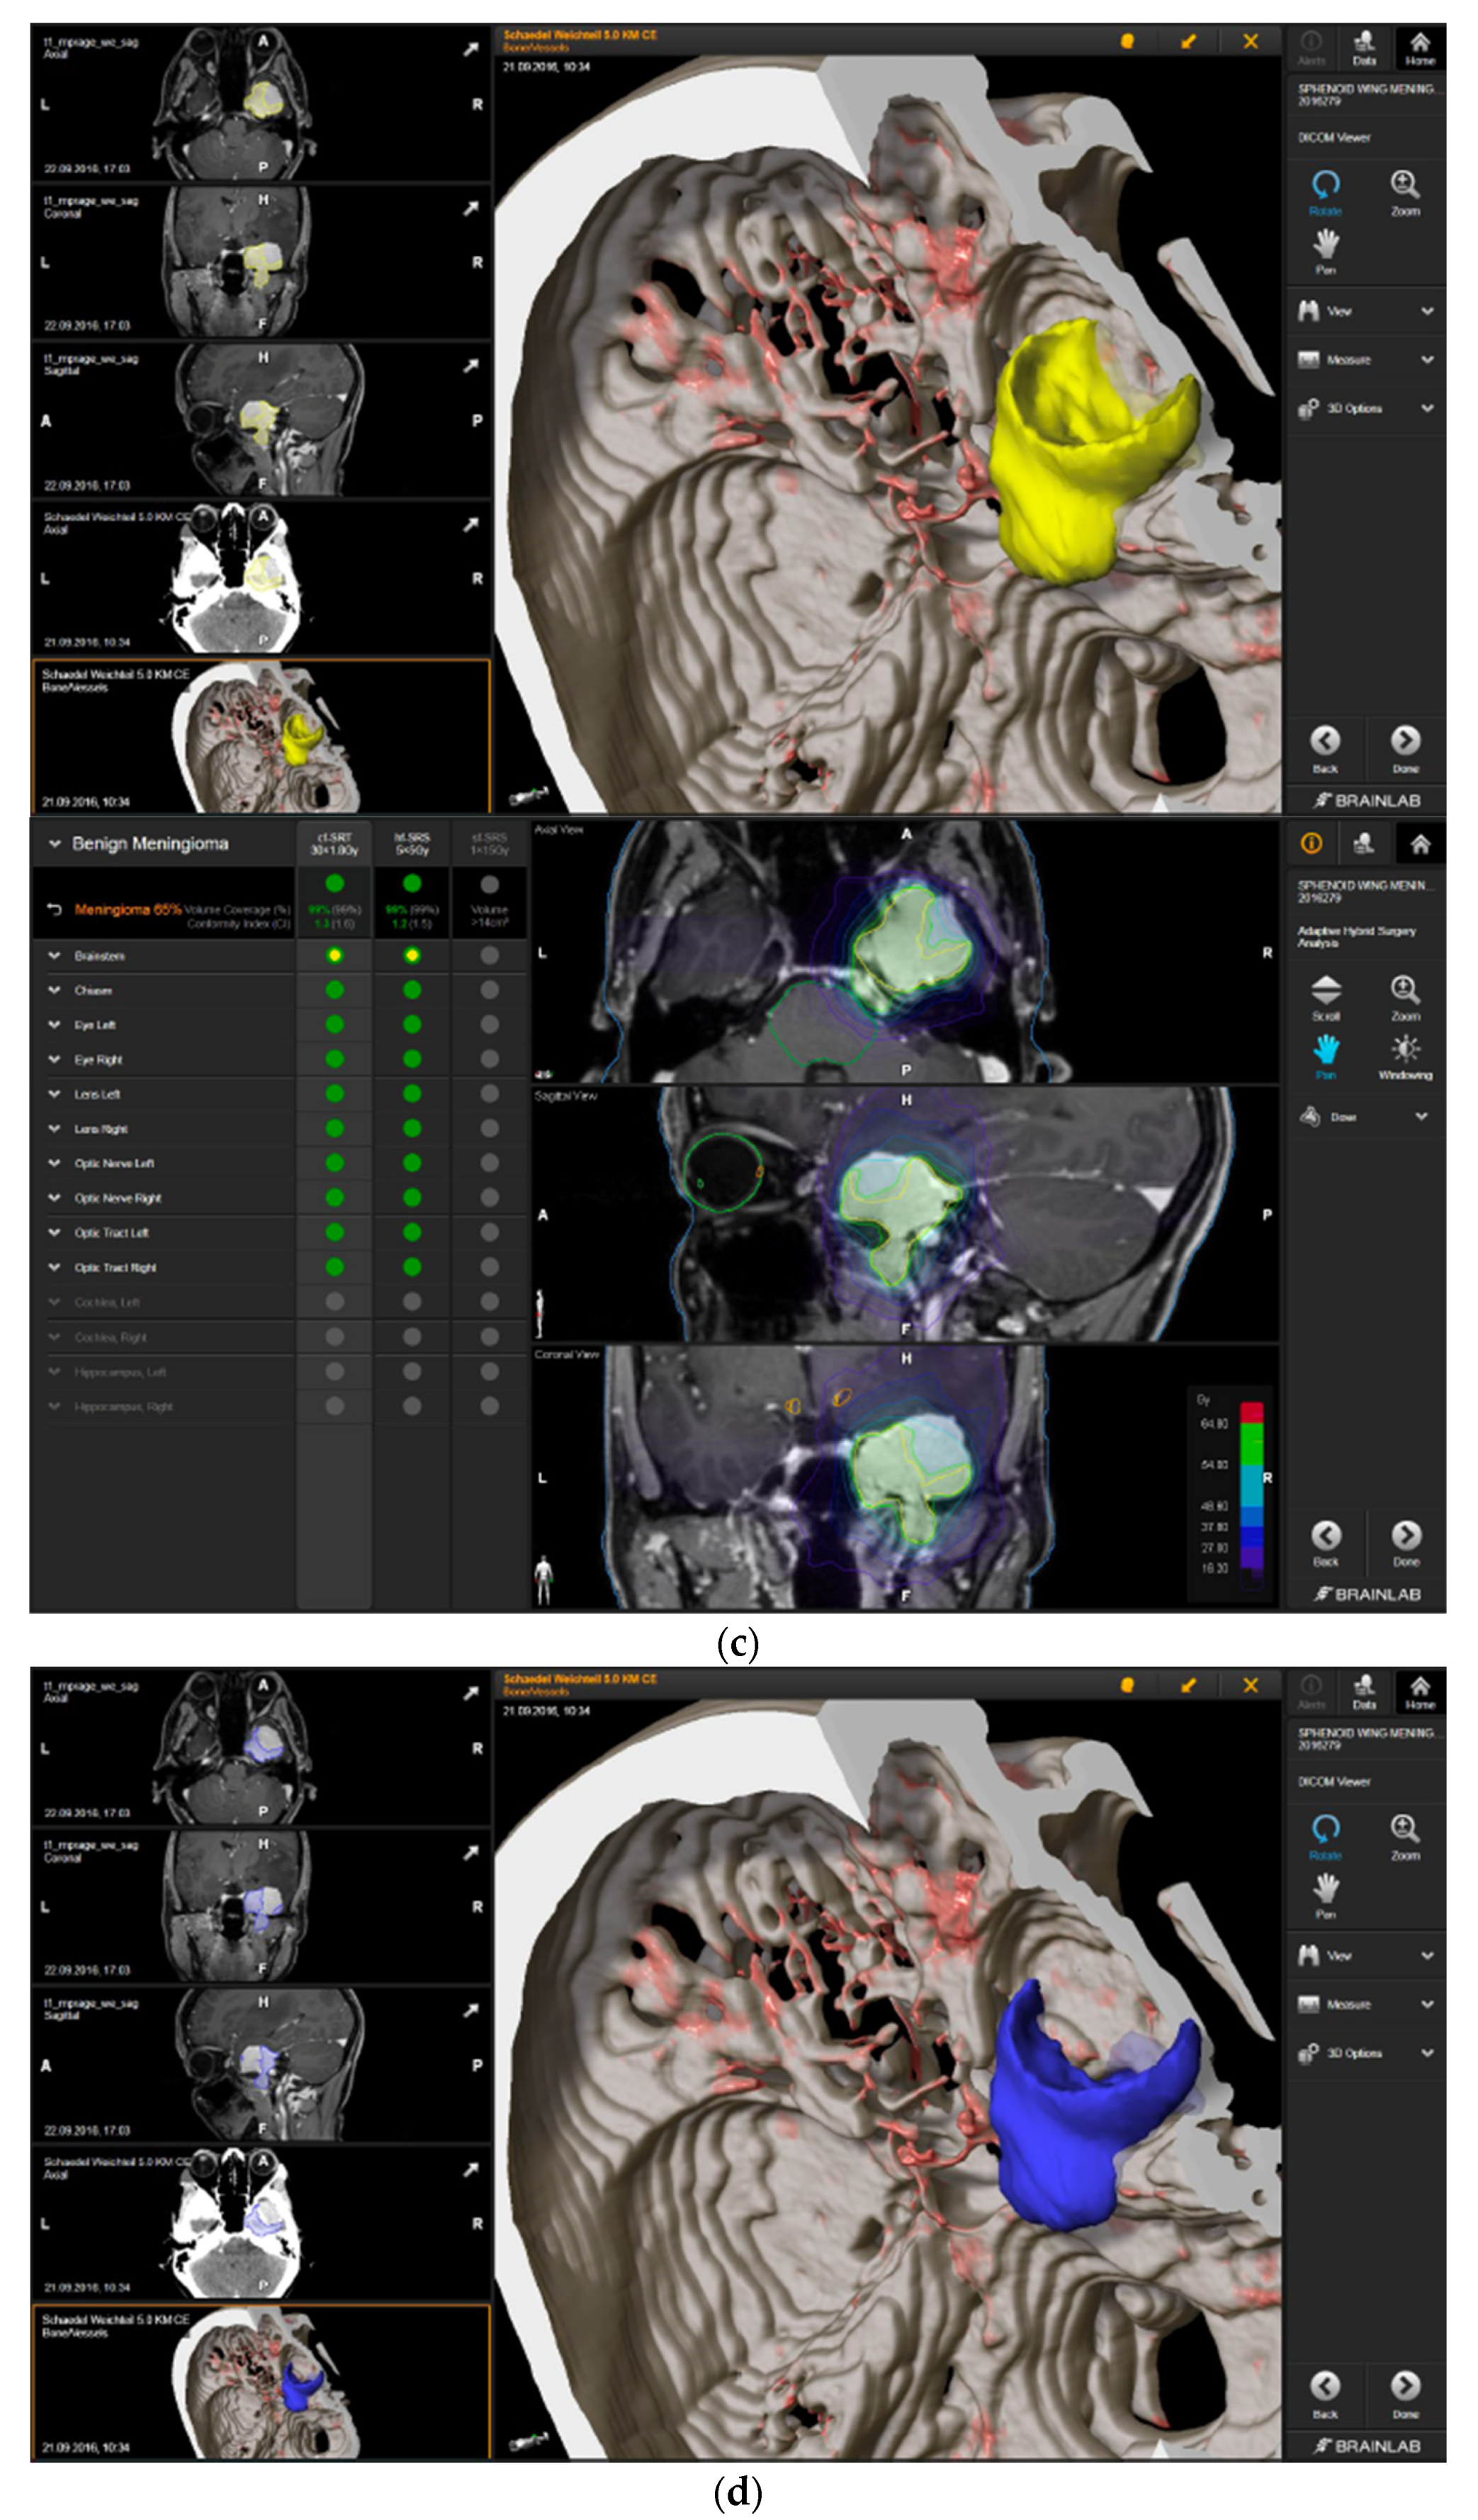

Figure 3.

First representative case with AHSA-assisted tumor resection. (a) Preoperative MRI imaging of tumor (orange) and planned residual tumor volume (red). (b) Dose constraints in the AHSA software for conventional, hypofractionated radiotherapy, and radiosurgery planning for the preoperatively defined residual tumor volume. With this plan, conventional fractionated and hypofractionated radiotherapy were feasible, with effective tumor coverage.

—brainstem: max. dose is marginally safe, whereas mean dose is safe. For single fraction stereotactic radiosurgery, the tumor volume coverage seems effective, while the conformity index was indicating over-treatment.

—brainstem: mean dose is safe, while max. dose is unsafe;

—chiasm: mean dose is unsafe, while max. dose is safe;

—right optic tract: mean dose is unsafe, while max. dose is safe. (c) First intraoperative structure update (ISU) at the time point of 65% residual tumor volume, showing the tumor coverage and organ at risk constraints. At this stage of the resection, AHSA demonstrated that only conventional and hypofractionated radiotherapy were feasible.

—brainstem: max. dose is marginally safe, whereas mean dose is safe. (d) Second ISU acquisition and residual tumor reduction to 58%. (e) Third ISU acquisition with a reduction of residual tumor volume to 41%. Dose constraints for conventional, hypofractionated radiotherapy, and radiosurgery are demonstrated. At the final stage of the resection, the conventional and hypofractionated radiotherapy organ risk constraints were unchanged.

—brainstem shows that max. dose is marginally safe, whereas mean dose is safe. The single-dose stereotactic radiosurgery constraints show that:

—brainstem: mean dose safe, max. dose unsafe;

—chiasm: mean dose unsafe, max. dose safe;

—right optic tract: mean dose marginally safe, max. dose unsafe. (f) Fusion of intraoperative CT to final intraoperative ISU. (g) Preoperative and 3 months postoperative MRI imaging for planning of radiosurgery (5 × 5 Gy).